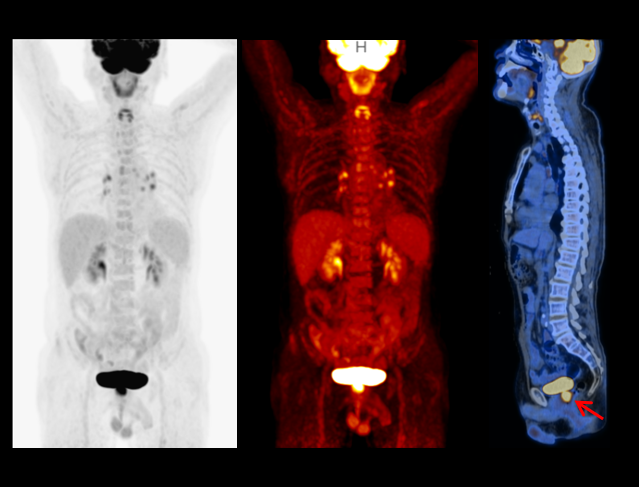

uMI 550搭载自主研发的新一代数字光导探测器,引领PET从「模拟化 」到「数字化 」的时代跨越,系统性能实现多重突破,以超低剂量实现高清成像,大幅提升病灶探测能力;全智能工作流,让临床诊断更精准、更高效、更关爱。

无需外接门控设备,基于PET原始数据,模拟呼吸曲线,提供数字门控图像及数据